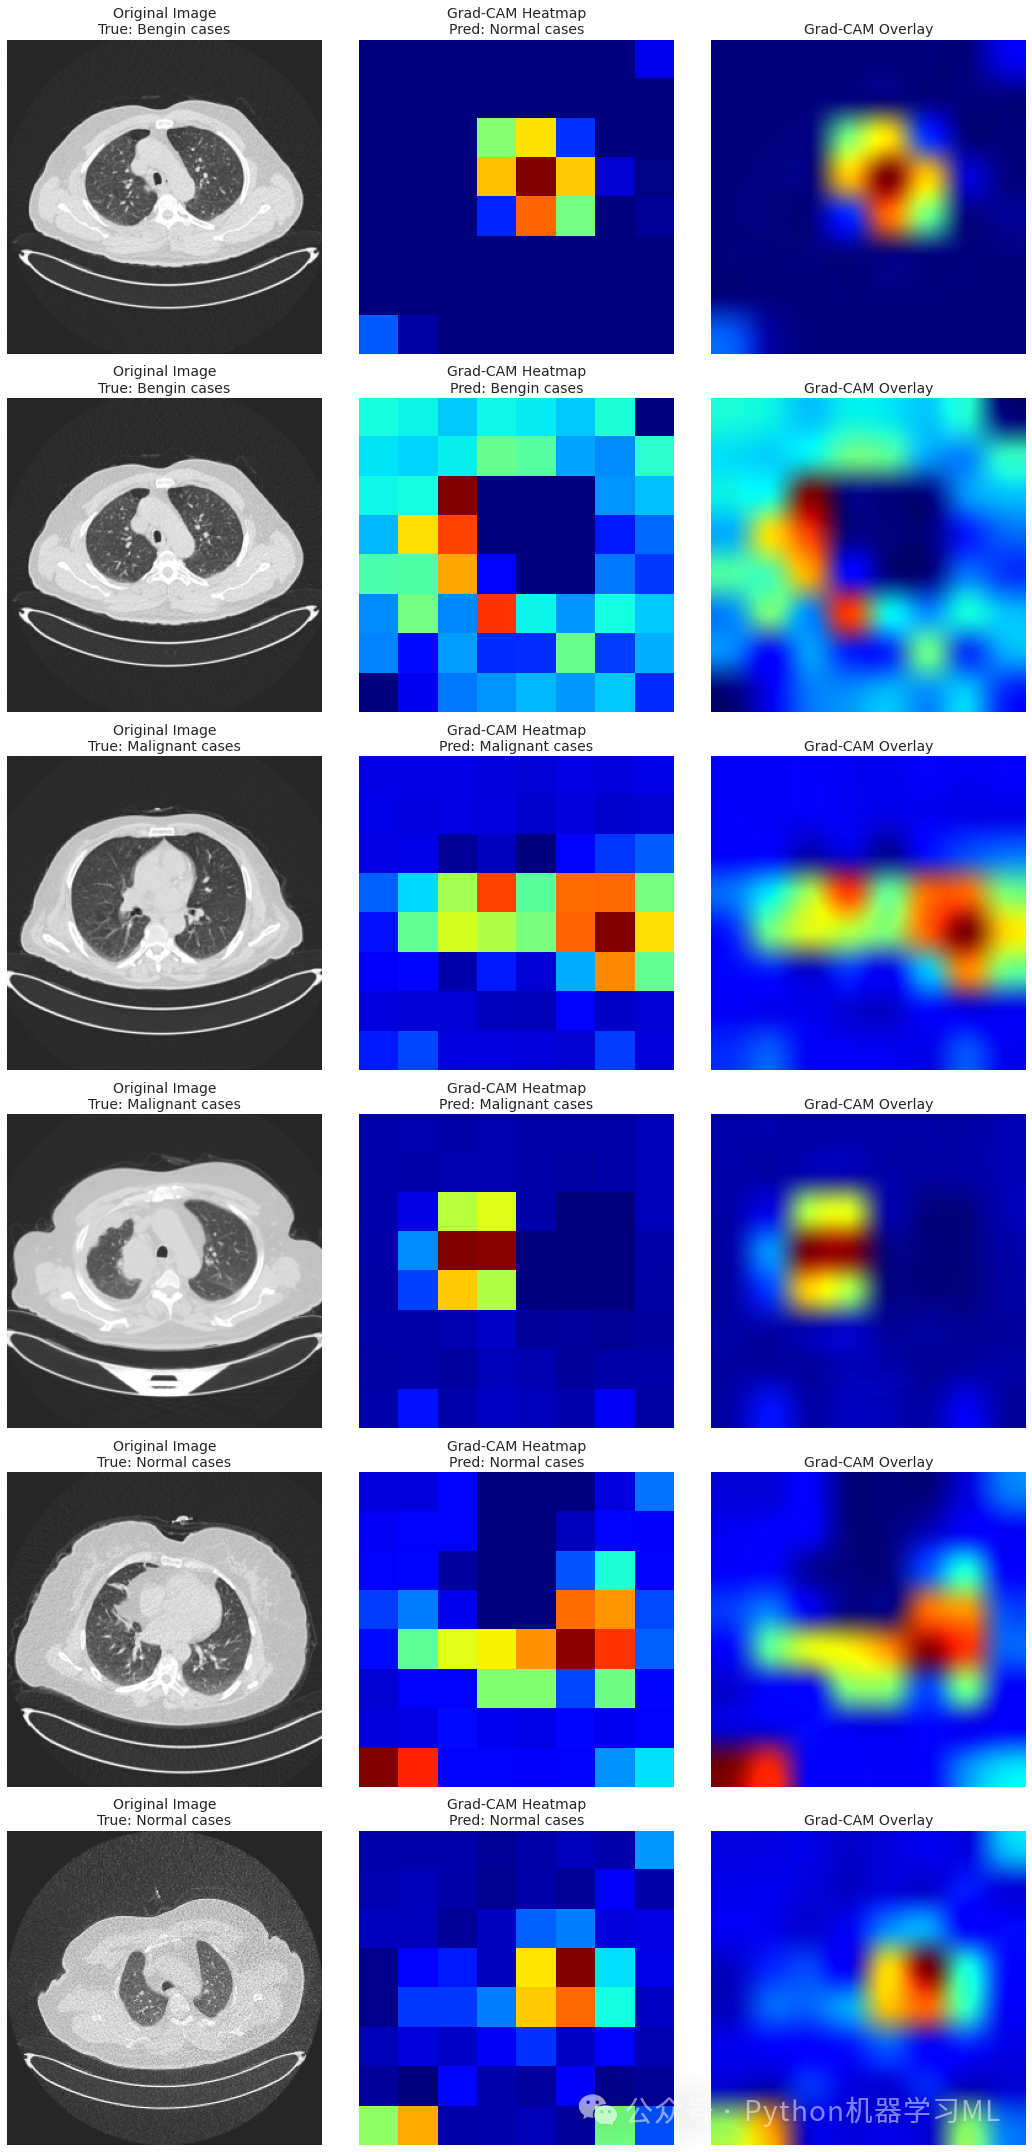

第七阶段:Grad-CAM模型解释实现

python# 添加一个更通用的Grad-CAM实现

import tensorflow as tf

import matplotlib.cm as cm

import matplotlib.pyplot as plt

defget_img_array(img, size):

# 扩展维度并确保使用正确的格式

img_array = np.expand_dims(img, axis=0)

return img_array

defmake_gradcam_heatmap(img_array, model, last_conv_layer_index=-4, pred_index=None):

"""

创建一个更通用的Grad-CAM热力图实现

参数:

img_array: 预处理后的输入图像数组

model: 训练好的模型

last_conv_layer_index: 最后一个卷积层在base_model中的索引(负数表示从末尾开始)

pred_index: 要生成热力图的类别索引(默认为预测的类别)

返回:

Grad-CAM热力图

"""

# 首先预测类别

preds = model.predict(img_array) # 使用模型进行预测

if pred_index isNone:

pred_index = np.argmax(preds[0]) # 如果没有指定类别,使用预测的最可能类别

# 获取模型中的base_model

base_model = model.layers[0] # 假设base_model是模型的第一层

# 获取最后一个卷积层

last_conv_layer = base_model.layers[last_conv_layer_index] # 获取指定索引的卷积层

print(f"Using layer '{last_conv_layer.name}' for Grad-CAM") # 打印使用的层名称

# 创建一个特征提取模型

feature_model = tf.keras.models.Model(

inputs=base_model.inputs,

outputs=base_model.get_layer(last_conv_layer.name).output

) # 创建从输入到最后一个卷积层输出的模型

# 创建一个分类模型

classification_model = tf.keras.models.Model(

inputs=model.inputs,

outputs=model.outputs

) # 创建整个模型的副本

# 使用特征提取模型获取卷积层的输出

with tf.GradientTape() as tape:

# 计算最后一个卷积层的输出

conv_output = feature_model(img_array) # 获取卷积层的输出

tape.watch(conv_output) # 监视卷积层输出以计算梯度

# 使用这个输出创建一个带有可监视梯度的新模型

# 这里我们使用一个简化模型来模拟从卷积层输出到分类结果的过程

model_input = tf.keras.Input(shape=conv_output.shape[1:]) # 创建输入层

x = model_input

for layer in model.layers[1:]: # 跳过base_model层

x = layer(x) # 应用后续的所有层

simplified_model = tf.keras.Model(inputs=model_input, outputs=x) # 创建简化模型

# 计算预测结果

pred_result = simplified_model(conv_output) # 使用简化模型计算预测结果

class_output = pred_result[:, pred_index] # 获取指定类别的输出

# 获取类别相对于卷积层输出的梯度

grads = tape.gradient(class_output, conv_output) # 计算梯度

# 计算梯度的全局平均值

pooled_grads = tf.reduce_mean(grads, axis=(0, 1, 2)) # 对梯度取平均值

# 将卷积层输出与我们计算的权重相乘

conv_output = conv_output[0] # 取出第一个样本的卷积输出

heatmap = tf.reduce_sum(tf.multiply(pooled_grads, conv_output), axis=-1) # 计算加权和

# 标准化热力图

heatmap = tf.maximum(heatmap, 0) / tf.math.reduce_max(heatmap) # 归一化热力图

return heatmap.numpy() # 返回NumPy数组格式的热力图

defsave_and_display_gradcam(img, heatmap, alpha=0.4, cam_path="cam.jpg"):

"""

叠加热力图到原始图像上

参数:

img: 原始图像(RGB)

heatmap: Grad-CAM热力图

alpha: 热力图透明度系数

cam_path: 保存结果图像的路径

"""

# 调整热力图大小以匹配原始图像

heatmap = np.uint8(255 * heatmap) # 转换为0-255范围的整数

# 将热力图应用到jet颜色图

jet = cm.get_cmap("jet") # 获取jet颜色映射

jet_colors = jet(np.arange(256))[:, :3] # 提取RGB部分

jet_heatmap = jet_colors[heatmap] # 应用颜色映射

# 创建一个具有RGB彩色热力图的图像

jet_heatmap = tf.keras.preprocessing.image.array_to_img(jet_heatmap) # 将数组转换为图像

jet_heatmap = jet_heatmap.resize((img.shape[1], img.shape[0])) # 调整大小以匹配原始图像

jet_heatmap = tf.keras.preprocessing.image.img_to_array(jet_heatmap) # 转换回数组

# 将热力图叠加到原始图像上

superimposed_img = jet_heatmap * alpha + img # 叠加图像

superimposed_img = tf.keras.preprocessing.image.array_to_img(superimposed_img) # 转换为图像

return superimposed_img # 返回叠加后的图像